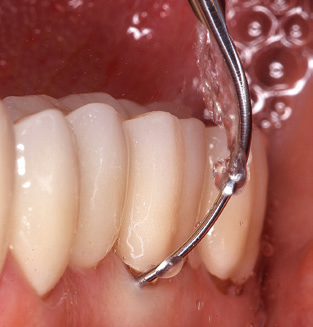

Das aktuelle Arbeitskonzept für die UPT

Nach der maschinellen Reinigung der Zahn und Implantatoberflächen erfolgt eine manuelle Instrumentierung der natürlichen Zahnoberflächen mit konventionellen Handinstrumenten. Bei der manuellen Reinigung ist insbesondere auf einen korrekten Anstellwinkel, eine ausreichende Schärfe, eine gute Abstützung und auf eine von apikal nach koronal gerichtete Arbeitsweise der Kürette zu achten. Zur Nachinstrumentierung der Implantatkonstruktionen sollten entweder Titan oder Carbonküretten verwendet werden (Abb. 8). Ergänzend zum Einsatz von Ultraschallgeräten können in der Erhaltungstherapie auch Pulverstrahlgeräte genutzt werden. Dabei ist jedoch zu berücksichtigen, dass diese Verfahren nicht zum Entfernen harter Beläge geeignet sind und daher die Verwendung von Hand oder Ultraschallinstrumenten nicht komplett ersetzen können. Abschließend erfolgt in jedem Fall eine mechanische Politur der zugänglichen Zahn und Implantatoberflächen mit Polierkelchen und Polierpasten (Abb. 9).